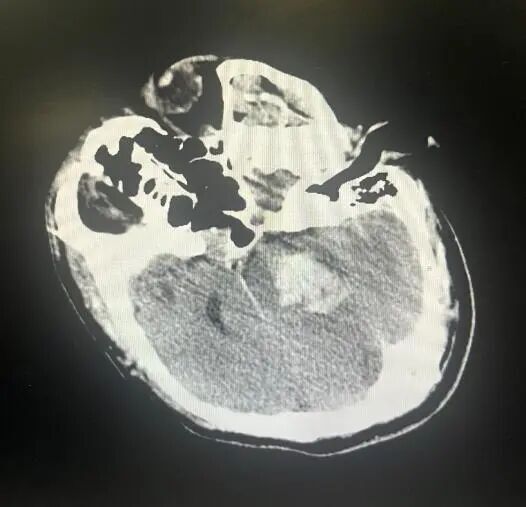

大众卫生报·新湖南客户端12月15日讯(通讯员 罗超)12月初的一天下午,急救车的警报声刺破了寂静。一名中年男性患者被推进了邵阳市中心医院神经重症病房,患者已陷入深度昏迷,针尖样瞳孔,面色发绀,自主呼吸已近乎停止。头部CT影像上,脑干区域那一团一颗葡萄大小的出血灶(约8毫升),却让所有在场医生面色凝重。这不是普通的脑出血,脑干出血8毫升,是一个被医学教科书被标注为“高死亡率”的数值。

8毫升的血液,在宽敞的脑室中或许可以被容纳,但在脑干这个狭窄、拥挤的核心要塞里,就是一场毁灭性的灾难。对于脑干出血,位置的重要性远远超过出血量本身。